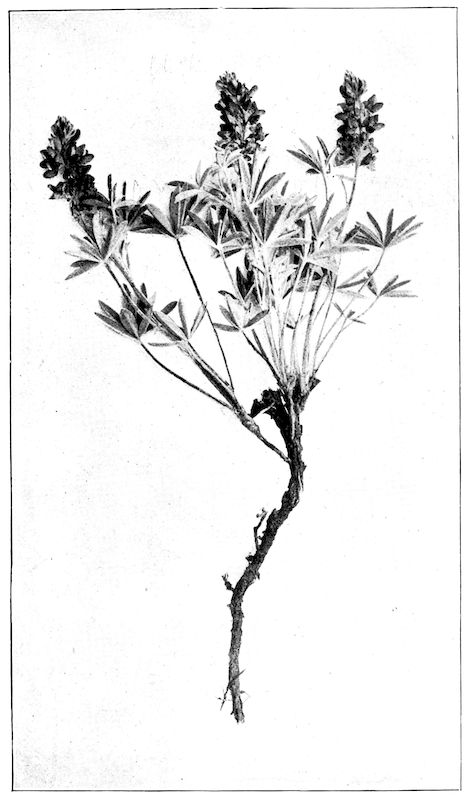

Fig. 1.—Rachitis in a young goat.

Rachitis is a disease of youth, and is common both to the human species and to all domestic animals. It is characterised by irregularities in development and by imperfect consolidation of the bones. The boundary between rachitis and osseous cachexia is difficult to define and in fact at the present moment the two diseases can scarcely be defined with exactitude. Rachitis again is often complicated with softening of the bones, disease of the limbs, arrested development, etc., but it must not be forgotten that although the irregularities in ossification and development of the skeleton are the symptoms most striking to the eye, they do not stand alone, and that from the point of view of development all the tissues, including the muscles, are more or less affected and that most of the physiological functions such as digestion and the secretion of urine are deranged.

Symptoms. The onset is absolutely insidious and the diagnosis of rachitis is never made until nutrition has long been abnormal.

This disturbance of nutrition is revealed by irregularity and abnormality in appetite, by difficulty in rising and moving about, and by the animals lying down for long periods. The subjects are feeble, sluggish and badly developed.

Next supervenes the second phase characterised by deformity of bones. This is of two kinds—deformity in the neighbourhood of joints (deformity or enlargement of the epiphyses) and deformity of the diaphyses. The former results from irregularity in ossification of the articular cartilages. The latter is followed by loss of rigidity in the bones of the limbs which, under the influence of the body weight and of muscular contraction, bend in different directions.

The bones appear of increased thickness principally towards the 6articulations. The latter are deformed, and on palpation are found to be surrounded by uneven and irregular growths.

The front limbs are distorted. In young pigs, lambs, and less frequently in foals, calves and dogs, the jaws become deformed, and mastication is rendered difficult.

The vertebral column may also be affected, and lordosis (bending downwards of the back) or skoliosis (lateral bending of the back) is somewhat frequent.

General development is always interfered with and the young creatures are generally dwarfed.